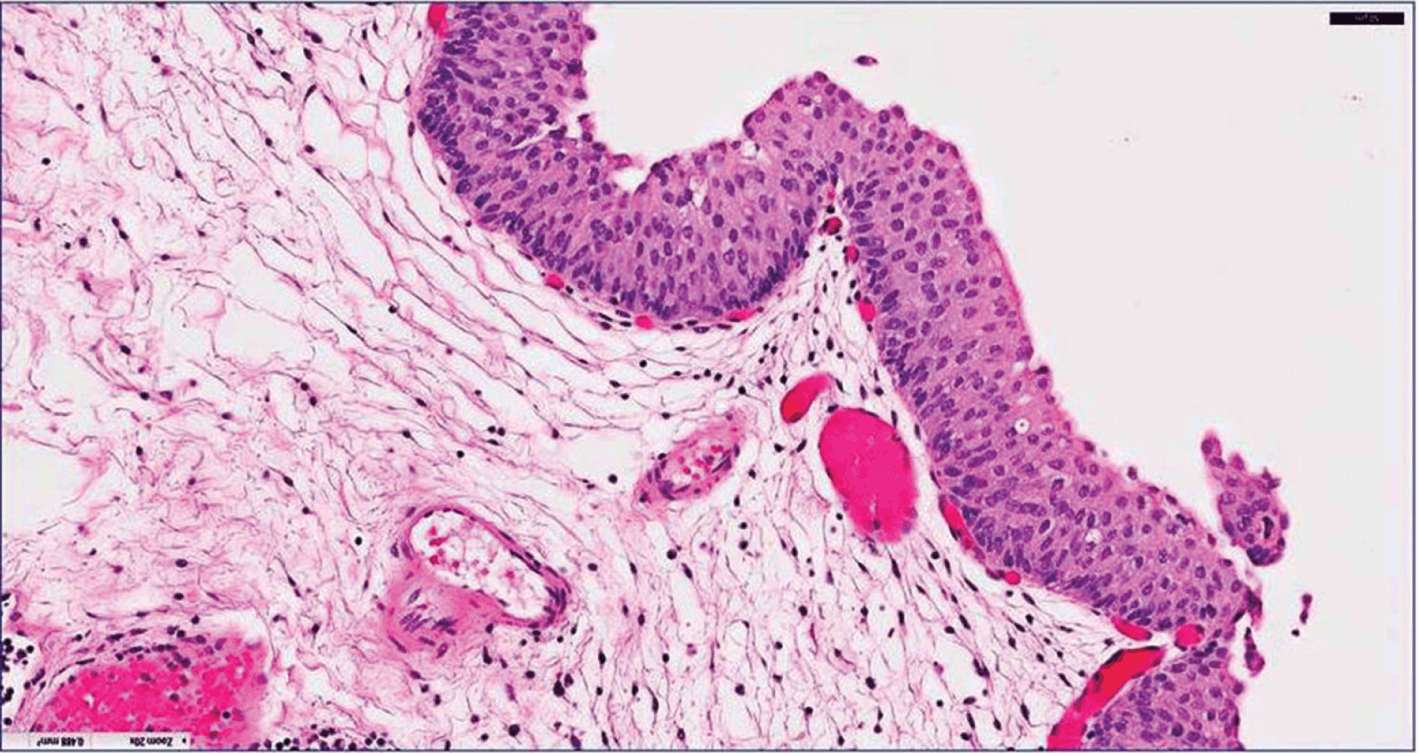

Patoloji raporu, TUR-T (transüretral rezeksiyon), sistoskopik biyopsi veya radikal sistektomi gibi işlemler sonucunda elde edilen tümöral dokunun, histopatolojik ve bazen immünohistokimyasal inceleme ile değerlendirilmesiyle oluşturulur.

| Histolojik Tip | Ürotelyal karsinom, skuamöz karsinom, adenokarsinom vb. |

| Tümör Derecesi (Grade) | Düşük (Low Grade) veya Yüksek (High Grade) |

| Evreleme (pT) | Ta, Tis, T1, T2, T3, T4 |

| Kas Tutulumu | Detrusor kas invazyonu olup olmadığı |

| Lamina propria invazyonu | Varsa T1 tanısı alır |

| CIS varlığı | Eşlik eden in situ hastalık |

| LVI | Lenfatik/kan damarlarına yayılım |